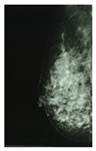

According to the Breast Imaging Data and Reporting System (BI-RADS), a PBD increase along a three-year period is associated with a higher breast cancer risk, and a PBD decrease with a smaller risk, than the risk when PBD remains unchanged. Two longitudinal BI-RADS breast density measurements (on current and previous mammography) may be better predictors of breast cancer risk than a single measurement [14]. The incorporation of breast density to the Gail model, a mathematical instrument that measures the risk of developing breast cancer in five years by identifying risk factors [15], increases predictive accuracy by statistical agreement from 0.607 to 0.642 [16]. The PBD BI-RADS classification is defined in Table 1, where illustrative cranio-caudal (CC) and mid-lateral oblique (MLO) mammography imaging samples for right and left breast are shown.

Table 1. BI-RADS classification and its relationship with mammography.

BI-RADS PBD ClassificationMammography

Right

(CCR)

Left

(CCL)

(MLOR)

(MLOL)

a = 0–25%

(Homogeneous adipose)

Sensors 22 02747 i001 Sensors 22 02747 i002 Sensors 22 02747 i003 Sensors 22 02747 i004

b = 25–50%

(Heterogeneous dispersed)

Sensors 22 02747 i005 Sensors 22 02747 i006 Sensors 22 02747 i007 Sensors 22 02747 i008

c = 50–75%

(Dense heterogeneous)

Sensors 22 02747 i009 Sensors 22 02747 i010 Sensors 22 02747 i011 Sensors 22 02747 i012